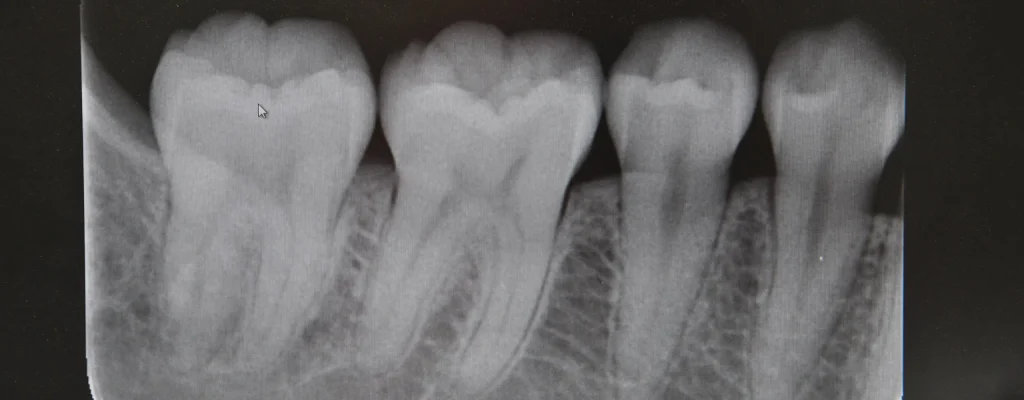

Grazie a questo esame, il dentista può visualizzare:

- la corona del dente

- la radice

- l’osso che sostiene il dente

- lo spazio tra un dente e l’altro

Si tratta di immagini molto dettagliate, fondamentali per una diagnosi corretta e per pianificare eventuali trattamenti.